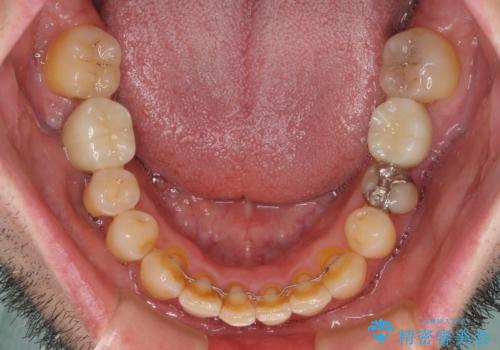

- 奥歯の痛みと前歯のデコボコを気にして来院された患者様です。

左右下顎の大臼歯は、ともに歯根が破折しており、抜歯が必要な状態でした。

放置したことで炎症による骨吸収が顕著であるため、骨造成を併用してインプラント埋入を行うこととしました。

咬み合わせは受け口傾向であり、上顎前歯の叢生が顕著であったことから、第1小臼歯抜歯による矯正治療も検討しましたが、下顎大臼歯を左右ともに抜歯するため、非抜歯による矯正治療を行うこととしました。